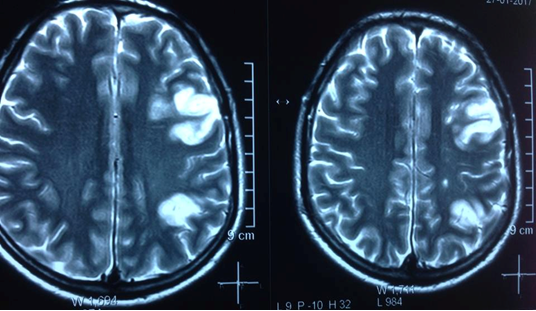

Hình ảnh chụp sọ não của bệnh nhân

Đáng chú ý là tiền sử sức khỏe của bệnh nhân bình thường, trước đó, bệnh nhân đã từng đến một cơ sở y tế lớn tại Khánh Hòa, nhưng chưa phát hiện cụ thể bệnh tình. Khi trở về nhà, bệnh nhân bị bất tỉnh, chỉ đến lúc cấp cứu vào Bệnh viện Tâm Trí mới phát hiện: Bệnh nhân bị nhồi máu đa ổ vùng bán cầu não trái.

Chụp MRI sọ não cũng cho kết quả: nhồi máu bán cầu đại não trái, kèm xuất huyết vỏ não thùy trán trái. Sau hội chẩn, các bác sĩ thống nhất kết luận: Bệnh nhân bị nhồi máu não đa ổ bán cầu não trái (nghi bệnh lý Moya – Moya).

Hình ảnh sọ não nghi là mắc bệnh Moya Moya